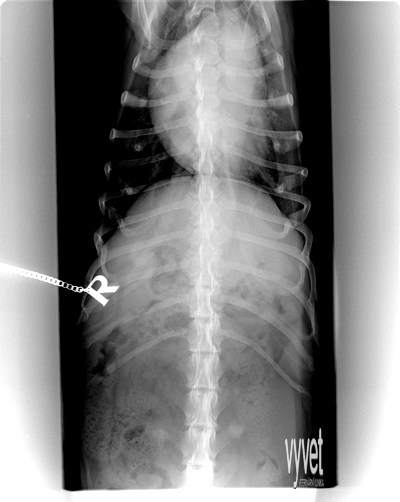

Spondyloartróza (srůst posledního bederního obratle s křížovou kostí) může a nemusí být příčinou bolestivosti v oblasti zad a nechuti k pohybu.